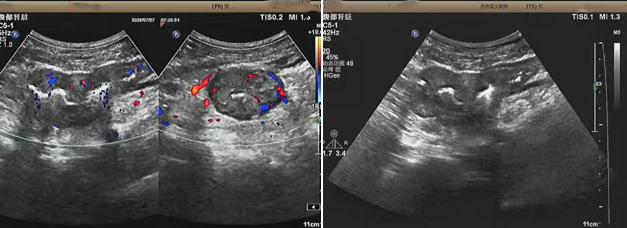

超聲檢查的結(jié)果進一步揭示了病情的細節(jié):下腹部偏左腸壁顯著增厚,原本清晰的層次結(jié)構(gòu)遭到破壞,周圍脂肪間隙變得模糊,網(wǎng)膜回聲也出現(xiàn)增強的現(xiàn)象,同時,腸腔狹窄的情況也得到了確認。經(jīng)過完善的檢查,最終將病變精準定位在乙狀結(jié)腸 - 直腸交界區(qū),并且對病變范圍及周圍浸潤情況做出了評估,這些關(guān)鍵信息為后續(xù)的診療工作提供了重要依據(jù),讓醫(yī)生們能更有針對性地制定治療方案。

我院超聲檢查在此次診療過程中展現(xiàn)出了顯著的技術(shù)亮點。一方面,它能做到 “明察秋毫”,通過高頻探頭可以清晰地顯示腸壁各層結(jié)構(gòu)的變化,為臨床判斷病變性質(zhì)提供了客觀、準確的依據(jù),讓醫(yī)生能更清晰地了解腸道內(nèi)部的病變狀態(tài)。另一方面,它實現(xiàn)了 “精準評估”,不僅準確找到了病變的位置,還能全面評估病變對周圍組織的影響,這對于協(xié)助醫(yī)生制定科學(xué)合理的治療方案起到了至關(guān)重要的作用,有助于提高治療的有效性和安全性。